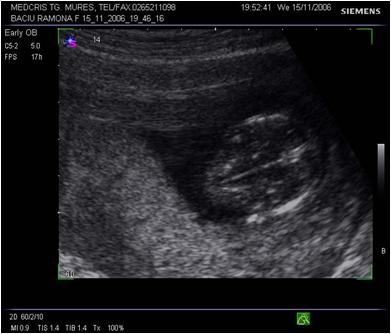

Fig nr 113. Acrania la o sarcina de 11 sapt.(ecografie abdominala ) Linia indica absenta calotei craniene

Fig. nr.114. Calota craniana normala ( cu sageata ) la ecografia abdominala. Se remarca proportia normala intre marimea capului si a fetei, spre deosebire de acrania din figura anterioara

Fig nr.115 Acrania la 11 saptamani. Linia indica plexurile choroide, fara invelisul calotei craniene, la ecografia transvaginala

Fig. nr.116. Craniu fetal la 12 sapt. Se remarca prezenta calotei craniene (sageata) in jurul plexurilor choroide